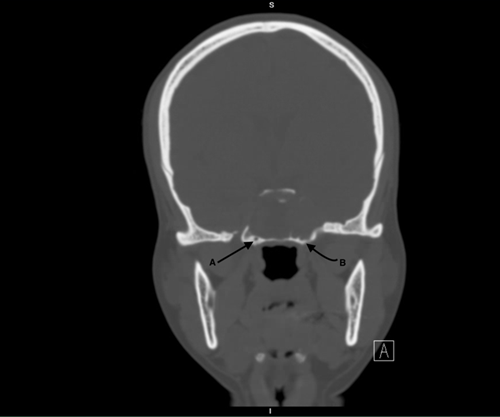

Postoperatively, the patient was closely monitored by ophthalmology. At follow-ups conducted one month and six months after surgery, she demonstrated stable optic neuropathy without any progression of her symptoms (Figure 4).

Figure 3: CT coronal view bone window showing bilateral vidian canals

Figure 4: T1 MRI axial view post resection

Figure 4